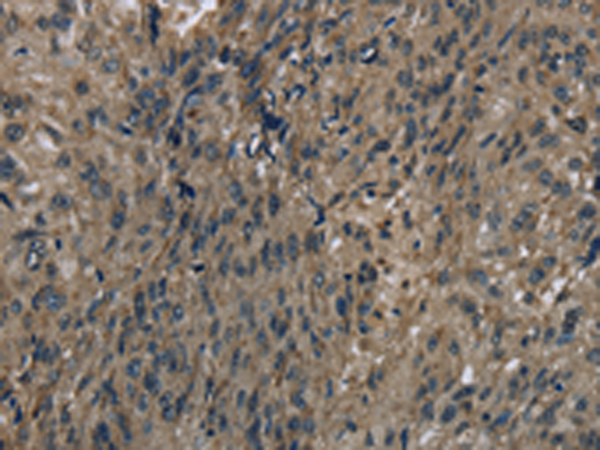

分类: 科研抗体货号: P01453别名: DHRS10; SDR47C1; retSDR3应用: WB,IHC反应种属: Human, Mouse